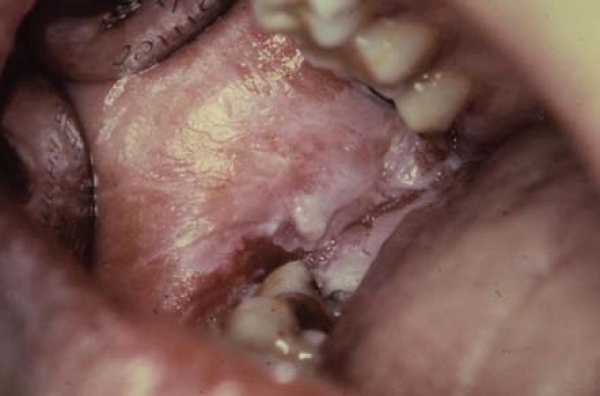

Diş hekimliğinin temel amacı; sağlıklı diş dokularının korunması ve kayıp dokuların tekrar kazandırılmasıdır. Sağlam diş dokularını koruma yönündeki konservatif yaklaşımlar, geleneksel kavite preparasyonu ile karşılaşılan problemleri ortadan kaldıracak daha konservatif yöntem arayışını da beraberinde getirmiştir. Prof. Dr. L. Şebnem Türkün Prof. Dr. Sevil Gürgan Dr. Xavier Goodarzian Doç. Dr. Zekai Yaman Piezoelektrik prensipler uyarınca olusturdukları ultrasonik vibrasyon vasıtasıyla kemik kesisi yapabilen aygıtlar pratikte piezoelektrik aygıtlar (piezocerrahi) olarak adlandırılmaktadır. Piezoelektrik aygıtlar, dental implantoloji başta olmak üzere ağız ve çene cerrahisi, plastik cerrahi, kulak burun Dt. Ali H. Özoğlu Yüksek teknoloji ile üretilen ve hekime çok sayıda renk seçenegi sunan kompozit rezinler sayesinde minimal invaziv restorasyonlar ile maksimum estetik elde edebilmek mümkün olabilmektedir. 25 yasındaki erkek hasta sağ üst kanin dişinin görünümünden sikayetçi olarak klinigimize geldi. Prof. Dr. Sevil Gürgan Günümüzde, posterior bölge dişlerinin restorasyonu amalgam, kompozit rezinler, cam iyonomer simanlar veya indirekt olarak; altın, kompozit ve seramik inley-onleylerle gerçekleştirilmektedir. Amalgamın olumsuz özellikleri, estetik diş hekimliğinde ve restoratif Dr. Betül İLHAN, Prof. Dr. Hülya ÇANKAYA, Prof. Dr. Pelin GÜNERİ Ağız boşluğu ve farenkste en sık karşılaşılan malignansi, her yıl yaklaşık 350,000 kişide belirlenen ve dünyada 68,000 kişinin ölümüne neden olan (1) skuamöz hücreli karsinomadır (2,3). Dr. Brock Rondeau Amerikan Diş Hekimleri Birliği (ADA) populasyonun %34’ünün TM disfonksiyonu belirti ve semptomlarına sahip olduğunu tahmin etmektedir. ADA diş hekimlerinin TM disfonksiyonunun tanı ve tedavisinde yetenek sınırları boyunca öncelikli sorumluluğu olduğunu da ifade etmiştir. Prof. Dr. A. Ersan Ersoy Protetik diş hekimliğinde, dişlerin ve diş eksikliklerinin restorasyonunda temel felsefe, hastanın estetik beklentilerinin ve fonksiyonel gereksinimlerinin yerine getirildiği en konservatif yöntem ve materyallerin kullanılmasıdır. Bunlara üretim süresi ve maliyet de eklendiğinde, günümüzde halen bu özellikleri tümüyle taşıyan bir materyal bulunmamaktadır. Doç. Dr. Filiz Namdar Pekiner Sir James Paget tarafından 1851’de “leukokeratosis”, 1870’de ise “icthyosis” olarak isimlendirilen oral lökoplaki (OL) ‘nin ilk ve tam olarak tanımı 1877’de Macar dermatolog E. Schwimmer tarafından tersiyer dönem sifilizde dildeki beyaz değişiklikleri anlatmak amacıyla yapılmıştır (1-4). Prof. Dr. Cem Şener Canlı bilimi teknolojinin gelişimi ile sürekli kendini yenilemekte ve her geçen gün medikal alanda akla gelmedik yenilikler ile ortaya çıkmaktadır. Hastalıkların tedavisi için doğada bulunan bazı maddelerin ve bitki esaslarının yanı sıra Fleming’in penisilini keşif etmesinden sonra Doç. Dr. Zekai Yaman Doğal dişlerin kaybını takiben alveoler kretlerde izlenilen ve implant tedavisini etkileyebilen rezorpsiyonların tedavisinde kemik greftleme yöntemleri başta olmak üzere, yönlendirilmiş kemik rejenerasyonu, kret ayırma ve alveoler distraksiyon gibi çeşitli yöntemler tanımlanmıştır. Prof. Dr. Betül KARGÜL Günümüzde Diş Çürüklerinde; Dental Materyallerde ve Teşhis Sistemlerindeki; bilimsel gelişmeler diş hekimliğine yaklaşımı değiştirmiştir. Çürükten korunmanın çürüğün tedavi edilmesinden daha büyük bir kazanç olduğu görüşü giderek yaygınlaşmaktadır. Prof. Dr. Nevin Büyükakyüz Dr. Murat Öztürk Botulinum toksin tıpta ve diş hekimliğinde geniş uygulama alanına sahip bir nörotoksindir. Bu derlemede, botulinum toksinin yapısını, etki mekanizmasını ve diş hekimliğindeki kullanım alanlarını literatürler aracılığıyla incelemeyi amaçladık. |